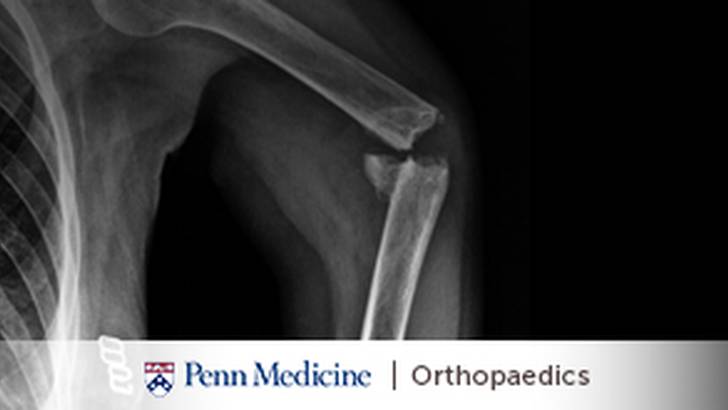

Then on the flip side we have something called cold trauma or elective trauma. This is more of what you would consider run-of-the-mill trauma. These are things like ankle fractures, wrist fractures, shoulder fractures, where the outcome is not dependent on the timing of intervention but rather, I would argue, the quality of the intervention when it's performed. And as we move towards all these changes in healthcare, things like bundled payments, quality of care payments, this is going to become even more important: What's the level of care that you're receiving? And so, as we look at some of these types of injuries, the ones that need acute attention are the ones where clearly the patient will have a detrimental effect. One of the classic ones that we talk about is the geriatric hip fracture. For instance, our goal or our goal has become to fix these within 24 hours of presentation because we know that if we can fix a senior person with a geriatric hip fracture, femoral neck intertroch (sic) and get them mobilized within 12 to 24 hours, that we significantly decrease their morbidity and their mortality at 30 days, 90 days and 1 year. Now, when you think about a hip fracture, you realize that's not that big of an injury. It's a low energy fall. It's not like an open tibia fracture or an open femur fracture or a pelvic fracture. True, but we know that the systemic effect from that hip fracture is tremendous, and the immobilization and the delay to surgery can be the cause of a high morbidity and mortality. So, there are definitely injuries on that spectrum that you may not consider hot that we deem important because the timing is so important. So, I think there's that big differentiation between hot trauma or hot injuries and cold trauma or more elective trauma where you can, for lack of a better word, you can electively choose to have your fracture fixed.